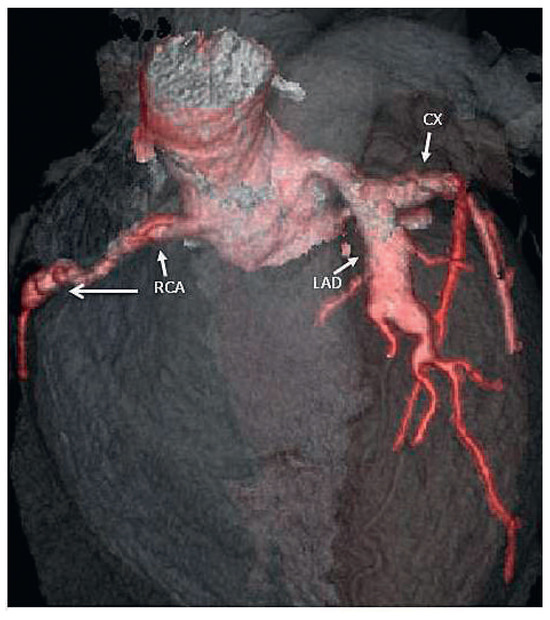

On the tenth day, we performed transthoracic echocardiography (Figure 1 and Figure 2), which revealed normal biventricular size and function, without hypokinesia. There was no pericardial effusion, no valvular disease, but a proximal enlargement of the left anterior descending coronary artery (LAD) was visualised. On the same day, because all these elements suggested Kawasaki disease (KD), treatment with intravenous polyvalent immunoglobulin (IVIG 2 g/kg as a single infusion: Privigen 70 g) and high-dose aspirin (80 to 100 mg/kg/d: 750 mg four times a day for eight days) was started, with rapid resolution of symptoms and apyrexia within 24 hours. Cardiac computed tomography (CT; Figure 3) showed three-vessel aneurysmal coronary artery disease (CAD) including a giant aneurysm of the proximal LAD (9 mm), an aneurysm of the circumflex artery (6 mm) and two aneurysms of the right coronary artery (4 and 5 mm). There was no vascular involvement in the cerebral and abdominal magnetic resonance imaging (MRI).

Figure 1.

2D echocardiography (* = left anterior descending artery aneurysm).